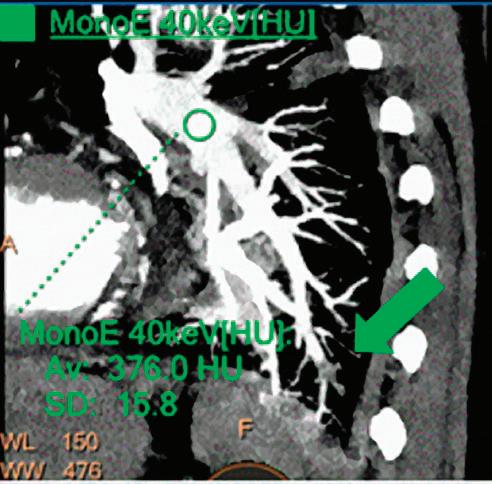

CT breath-hold results in a poor enhancement of the pulmonary arteries on the displays from left to right: monoenergetic 70 keV, monoenergetic 55 keV, monoenergetic 40 keV, and Z effective map showing a perfusion deficit of the lung parenchyma (white arrow). When decreasing the energy, the iodine attenuation is progressively boosted and reveals the presence of a thrombus (colored arrows) in a sub-segmental pulmonary artery corresponding to the territory of the perfusion deficit. (c) Monoenergetic 200 keV reduces beam hardening from dense contrast medium compared to conventional CT images.

Once the pair (αp, αc) is calculated for every voxel, and since fp(E) and fc(E) are known functions of energy, one may synthesize monochromatic images at different energies. These images can be used for routine diagnosis similar to conventional images. With a single scan at 120 kVp (or 140 kVp for obese patients), a dual-layer spectral CT acquisition allows the reconstruction of virtual monochromatic images from 40 keV up to 200 keV, in increments of 1 keV. The minimum of 40 keV was chosen in order to stay above the k-edge of the most common materials including iodine (iodine k-edge = 33 keV). If the scan is performed at 120 kVp, the conventional CT images of a typical-size patient will display an attenuation corresponding to the average of the X-ray spectrum (˜70 keV in a body scan) but with beam hardening artifacts from dense structures (like bones) which are due to the polychromatic nature of the X-ray beam. Since the photoelectric effect is dominant at lower keV, and is relatively high for high Z materials, low keV imaging (below 70 keV for body) can be used to enhance the absorption of high Z material such as iodine (Z=53), compared to the conventional CT images.15,16 This can be of particular interest to enhance the iodine uptake for patients with renal dysfunction, where the total injected volume of iodinated contrast medium is very limited. This attenuation boost can also be very useful in the case of a missed injection (Figure 2a and b). Compton scattering on the other hand is dominant at higher keVs and does not exhibit a strong relationship with Z. High keV imaging will then be of particular interest to minimize the absorption of high Z materials and minimize all types of associated artifacts (metal beam hardening from metal implants, beam hardening from dense contrast medium, blooming of stents or calcium, etc.) (Figure 2c).17,18,19

Virtual monoenergetic images obtained from the IQon Spectral CT scanner have low noise across the entire spectrum of energies,20 and this noise is lower than in conventional images due to the spectral reconstruction processing that includes noise suppression algorithms that make use of the additional spectral information. This provides significant SNR and CNR improvements compared to conventional polyenergetic images. The low noise of monoenergetic images at various energy levels makes them usable at all energy levels, particularly at low energies for enhancing vascular contrast or improving lesion conspicuity and at higher energies for decreasing artifacts.